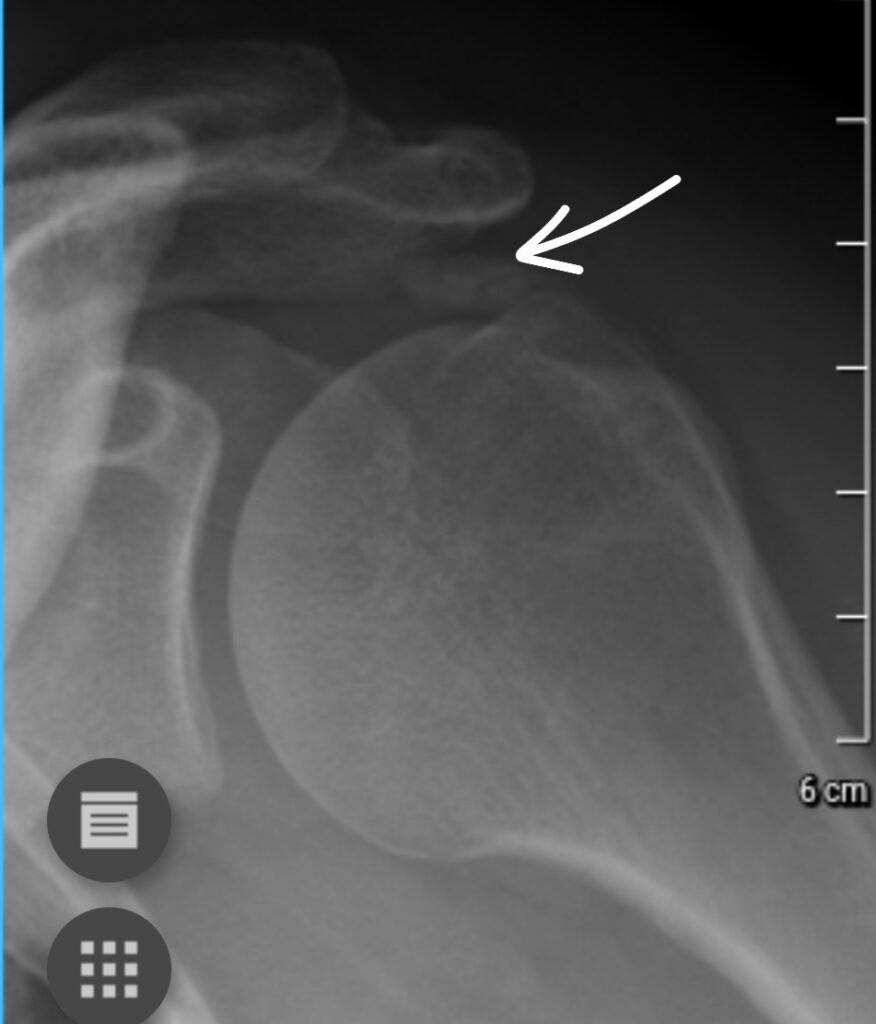

CALCIFIC TENDONITIS

In some patients the rotator cuff calcifies. This is a painless process. Once the calcium deposit starts to dissolve it becomes very painful. Treatment consists of painkillers, hot packs, steroid injection and, if conservative measures fail, surgery. At the time of surgery the calcific deposit is poked with a needle and the liquefied calcium drains. Usually very effective to manage the pain, though not always instantaneous.